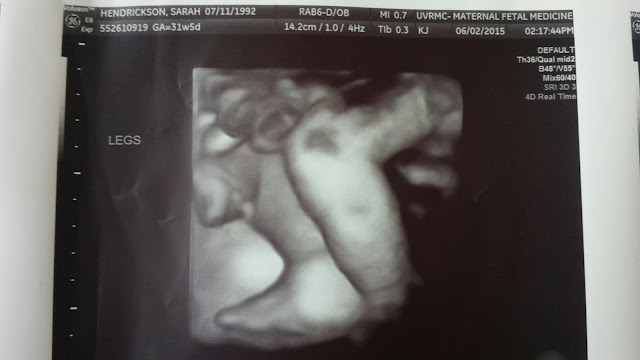

I had felt her move very gently only three times on Wednesday so when I woke up on Thursday I went straight for the sugary cereal in hopes that would wake Charlotte up and get her moving. I ate and waited. I grabbed a cold water, drank half and laid down on my left side and waited. I started to panic so I dropped Owen off with Amanda and went in to the hospital.

They did a NST (Non Stress Test) and monitored her heart rate for about 40 minutes. Everything was fine. It was a little on the slow side but they figured that was because she was sleeping. I left feeling better but not completely satisfied. I still felt like something was wrong. I only remember feeling her move one or two more times the rest of the day.

10:00am

I woke up and went for the cereal again but no movement. I tried pushing her around a little and nothing. It was my dad's birthday on Friday so we all (my family) met up for a surprise lunch for him. We got there and I still hadn't felt anything. I really tried to keep calm but I was getting really panicked. We finished eating, I left Owen with Amanda again and had my mom take me to the hospital to do another NST just to make sure, while my dad and Chris headed back to work. I knew she was still alive but I also knew something else was wrong.

The nurse took me back and put the monitors on to listen to Charlotte's heart. Within a few minutes we watched her heart rate drop from the 120's to the 80's. Before I could yell to the nurse that it looked a little to low she came running in. She said "Wait, let's watch it for a minute".

It dropped again. The nurse ran out and grabbed the closest doctor and had her look at it. Within a minute the doctor looked at me and said "This isn't good, we've got to get you to Labor and Delivery".

Here is one of the pictures Stacy took. Obviously little miss had some kind of syndrome that we didn't even know about. I think they ruled out Downs but she had something else. The hospital asked if they could do an autopsy because of her defect and hernia for research. They wanted to do a placental autopsy also to see why she wasn't getting enough oxygen because they think she hadn't been getting enough for a few days. Which lines up perfectly with my feeling of something being wrong. We told the hospital of course. Letting them do that autopsy might help a future family.